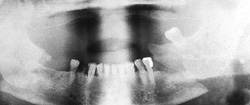

The primary purpose of the consultation is the outpatient follow-up treatment and care of patients who have undergone surgery following bone injuries to the upper and/or lower jaw. In addition to patients with fractures of the facial skull, patients with injuries to the teeth and facial soft tissues are also followed up.

Osteosynthesis procedures are performed at our clinic according to modern international standards. Mini and micro plates made of titanium and special medical steel are used to stabilize the fractured bones. Especially for the treatment of temporomandibular joint fractures a joint plate was developed in our clinic. The development and application of resorbable osteosynthesis materials is at the same time a research task of the clinic.